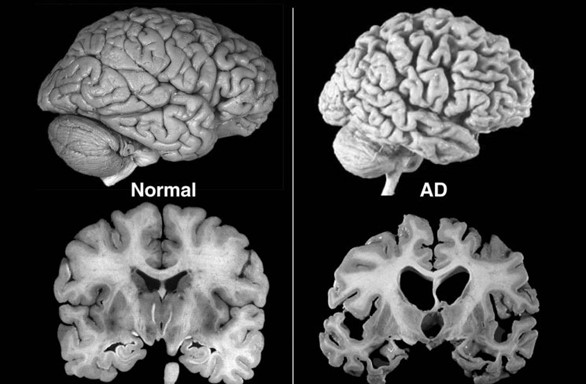

Brain atrophy in women and men with amnestic mild cognitive impairment

Brain atrophy rates and patterns differ between genders along the disease continuum; in mild cognitive impairment, brain atrophy is more rapid in women than in men.